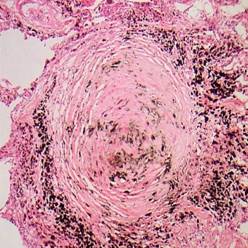

显微镜下见矽结节呈圆形或星芒状,中央由已发生玻璃样变性的胶原纤维组成,胶原纤维呈同心圆排列。结节周围有不同比例的网状纤维、巨噬细胞、成纤维细胞和浆细胞包绕,似晕状,晕越大,病灶越活跃。用偏光显微镜可以鉴定矽结节内和沉积在肺组织里的石英颗粒。

在形态学上,矽肺有三种类型:单纯的结节性矽肺、球形矽肺以及急性矽肺。结节性矽肺特征是肺实质表现为呈灰黑色的、且被严密包绕着的、直径为0.5~5mm的结节。如果合并有结核,这些结节可以发生空洞化。肺门淋巴结常肿大且可以有钙化,典型的钙化是出现在结节的边缘,呈“蛋壳样钙化”。在显微镜下,具有诊断性意义的病变是矽肺结节或矽肺岛,这些病灶通常位于呼吸性细支气管旁。矽肺岛的中央含有一呈螺纹状的、透明的、由非细胞组成的胶原块,其外周是巨噬细胞及浆细胞层。在组织形态学上,可见到数量不等的尘埃,如果其中的石英浓度很高,颗粒较小,则很少量的尘埃也可以产生严重的纤维化。如果持续暴露于粉尘,将使得已存在的结节的数量和大小增加;但即使在停止暴露于相应环境后,结节仍可以继续扩大,这是由于巨噬细胞的外周性位移以及纤维化继续形成之故。